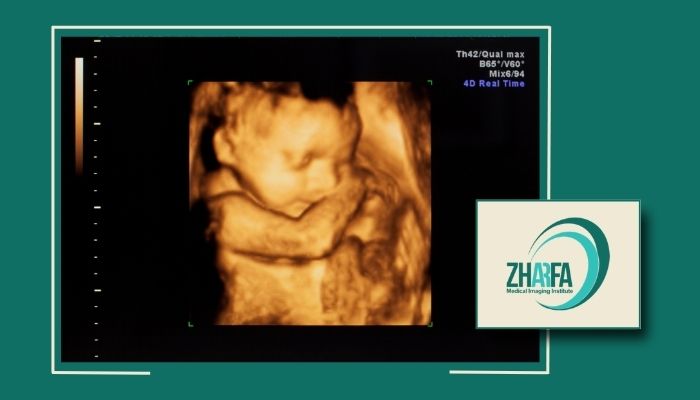

سونوگرافی سهبعدی در دوران بارداری

مشاهده دقیق جنین: این روش امکان دیدن چهره، حرکات و اندامهای جنین را فراهم میکند.

تشخیص ناهنجاریها: میتوان مشکلات مادرزادی مانند شکاف لب یا اختلالات اندامی را با دقت بیشتری بررسی کرد.

بررسی رشد و تکامل: میتوان رشد استخوانها، اندامها و حرکات جنین را ارزیابی کرد.

آرامش خاطر والدین: دیدن جنین به شکل واضح حس نزدیکی و اطمینان بیشتری برای مادر و پدر ایجاد میکند.

تفاوت تصویر 3d با 2d و 4d

دوبعدی: تصاویر سیاه و سفید و پایه برای تشخیصهای عمومی.

سهبعدی: نمایش حجمی و دقیق با جزئیات بالا.

چهاربعدی: همان سهبعدی است با قابلیت مشاهده لحظهای ویدیویی.